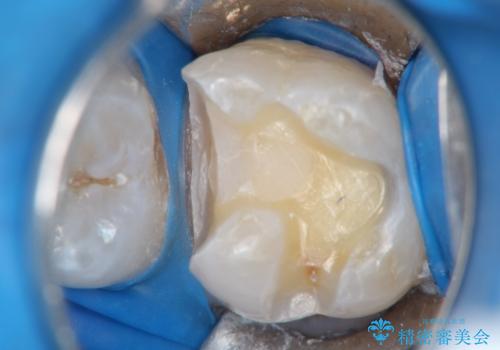

- 以前に被せ物の治療した箇所に汚れが溜まりやすいことを主訴に来院されました。

矯正治療を行なったのち、オールセラミッククラウンにて修復しております。

矯正治療はインビザラインで行なっております。